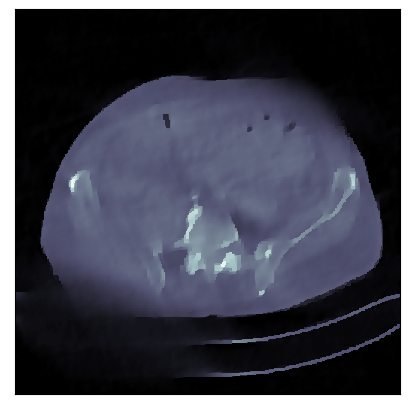

We consider the variational reconstruction framework for inverse problems and propose to learn a data-adaptive input-convex neural network (ICNN) as the regularization functional. The ICNN-based convex regularizer is trained adversarially to discern ground-truth images from unregularized reconstructions. Convexity of the regularizer is desirable since (i) one can establish analytical convergence guarantees for the corresponding variational reconstruction problem and (ii) devise efficient and provable algorithms for reconstruction. In particular, we show that the optimal solution to the variational problem converges to the ground-truth if the penalty parameter decays sub-linearly with respect to the norm of the noise. Further, we prove the existence of a sub-gradient-based algorithm that leads to a monotonically decreasing error in the parameter space with iterations. To demonstrate the performance of our approach for solving inverse problems, we consider the tasks of deblurring natural images and reconstructing images in computed tomography (CT), and show that the proposed convex regularizer is at least competitive with and sometimes superior to state-of-the-art data-driven techniques for inverse problems.